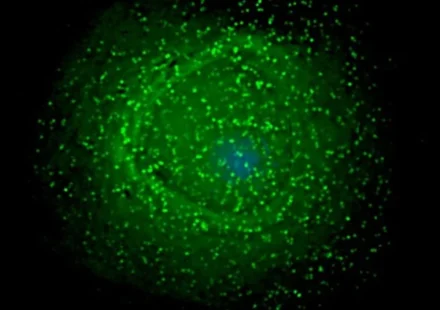

Ученые раскрыли одну из ключевых уловок вируса иммунодефицита человека (ВИЧ), которая позволяет ему десятилетиями скрываться в организме. Новое исследование проливает свет на то, где и как ВИЧ формирует свои латентные резервуары, что является важным…